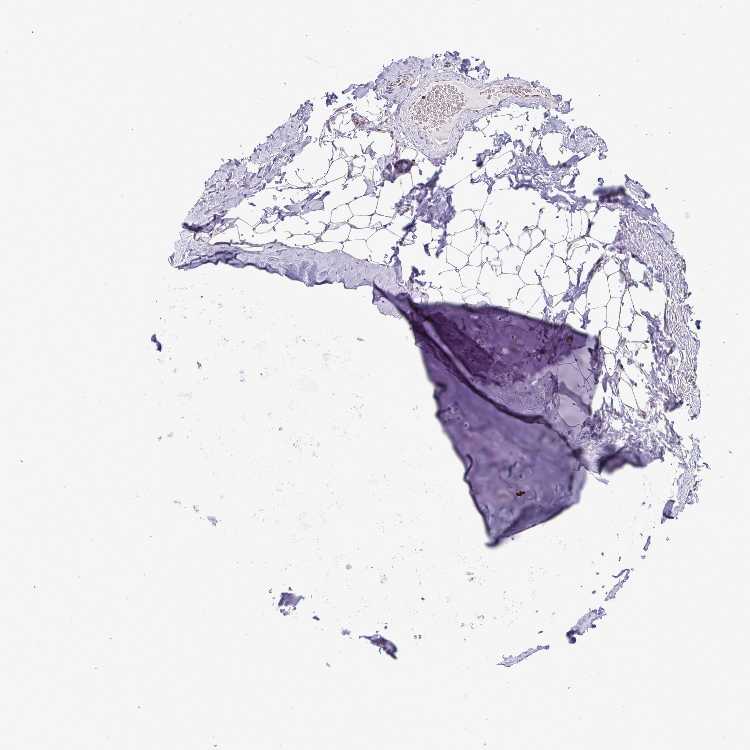

ADIPOSE TISSUE - Antibody stainingi

Antibody staining in the annotated cell types in the current human tissue is reported as not detected, low, medium, or high, based on conventional immunohistochemistry profiling in selected tissues. This score is based on the combination of the staining intensity and fraction of stained cells.

Each image is clickable and will lead to virtual microscopy that enables deeper exploration of all samples and also displays staining intensity scores, fraction scores and subcellular localization as well as patient and tissue information for each sample.

Antibody HPA003506Antibody HPA053314Antibody CAB037206

Adipocytes MediumNot detectedMedium